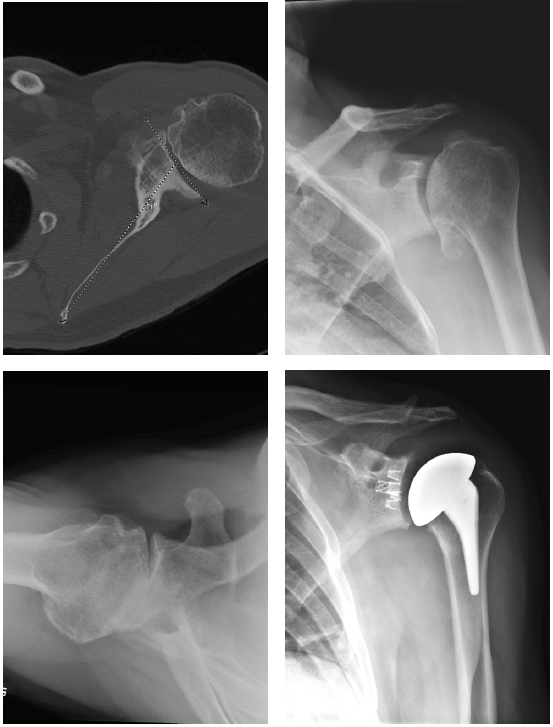

Patient 3: Revision of a failed anatomic total shoulder with loose humeral stem to reverse total shoulder arthroplasty

- The humeral stem was loose, so it was replaced with the short stem for the aggressive proximal geometry, which fit nicely and improved the proximal press-fit

- Revised an anatomic to a reverse, replacing stem from another company

- Significant glenoid wear led to augmented baseplate choice – superior posterior augment